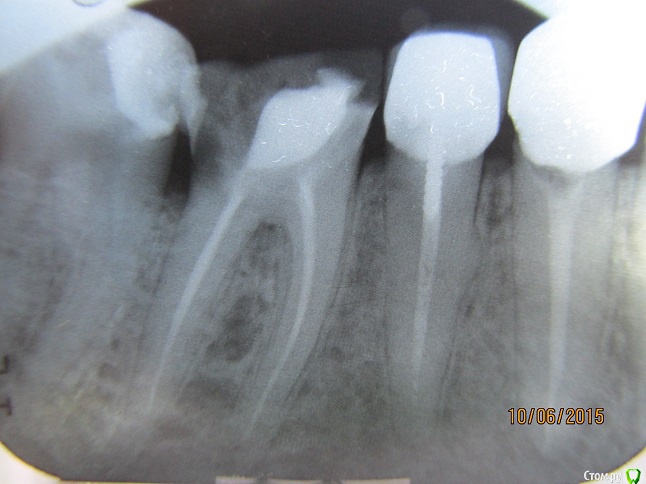

Борис Ф Опубликовано 11 июня, 2015 Поделиться Опубликовано 11 июня, 2015 (изменено) Имеем 6-й нижний зуб справа. У зуба практически не было коронки, но корень был здоров. Сделали мне т. н. "восстановление зуба с армирующими штифтами и светоотверждаемым материалом" с целью дальнейшей постановки коронки. За время, пока стоматолог делала мне зуб, я так и не понял, поставила ли она штифт. Я всегда этот момент замечаю, т. к. штифт вкручивают, и это чувствуется. Я заподозрил, что врач не поставила штифт вообще. Я сделал в другой клинике рентген отремонтированного зуба, и у меня появились вопросы. 1. Сколько штифтов обычно ставится в двухкорневой зуб? 2. Штифт стоит не в канале. Нормально ли это? 3. Штифт стоит с одного боку абы как. Выполняет ли он при этом армирующую функцию? 4. Вокруг штифта, особенно ближе к коронке, имеется область разрежения. Не означает ли это, что штифт просто вставлен в заранее просверленное отверстие без вкручивания? 5. Сформированная вновь коронка зуба вплотную прижата к соседним зубам. Как в отсутствие зазора ставить на зуб коронку? 6. Ночью зуб начал болеть. Нормально ли это? Прошу уважаемых врачей по возможности ответить на мои вопросы. Первый снимок - после лечения, второй - до. Изменено 11 июня, 2015 пользователем Борис Ф Ссылка на комментарий

Гарриевич Опубликовано 12 июня, 2015 Поделиться Опубликовано 12 июня, 2015 по теменайдите адекватного стоматолога и решайте вопросуже сейчас дистальная (задняя) сторона зуба разрушена практически на уровне кости 1 Ссылка на комментарий